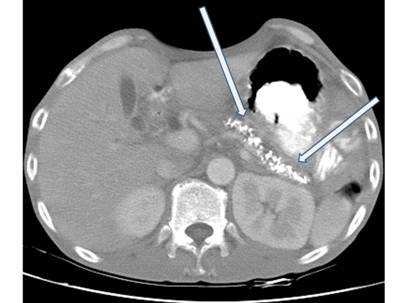

【107-2 醫學(三) 第74題】

一名酗酒男性因上腹悶痛和食慾不佳來求診,電腦斷層檢查呈現如圖,箭號所指之異常最可能是下列那一項診斷?

詳解

破題關鍵

這題的解題核心是從電腦斷層影像中辨識出胰臟的鈣化點,並結合病患的酗酒史,直接聯想到慢性胰臟炎。圖片中箭號所指的胰臟內高密度亮點就是關鍵線索。